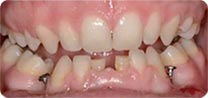

安卓健临床案例分享

单颗 多颗牙缺失、半全口牙缺失 ,假牙不适者